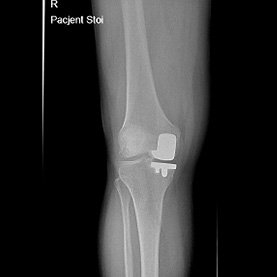

Endoproteza stawu kolanowego

Endoprotezoplastyka stawu kolanowego to skuteczna metoda leczenia zaawansowanej choroby zwyrodnieniowej kolana. Zabieg polega na chirurgicznym usunięciu uszkodzonych powierzchni stawowych i ich zastąpieniu nowoczesnym implantem – całkowitym lub częściowym – który przywraca funkcję stawu, poprawia jego stabilność i eliminuje ból. Leczenie to jest przeznaczone dla pacjentów z silnymi dolegliwościami bólowymi, ograniczeniem ruchomości, sztywnością kolana oraz brakiem efektów leczenia zachowawczego.

Endoprotezoplastyka kolana wykonywana jest z użyciem wysokiej jakości implantów, które dobieram indywidualnie do budowy anatomicznej pacjenta oraz jego aktywności życiowej. Nowoczesna technika operacyjna umożliwia precyzyjne ustawienie osi kończyny dolnej oraz uzyskanie stabilnego i trwałego efektu leczenia.